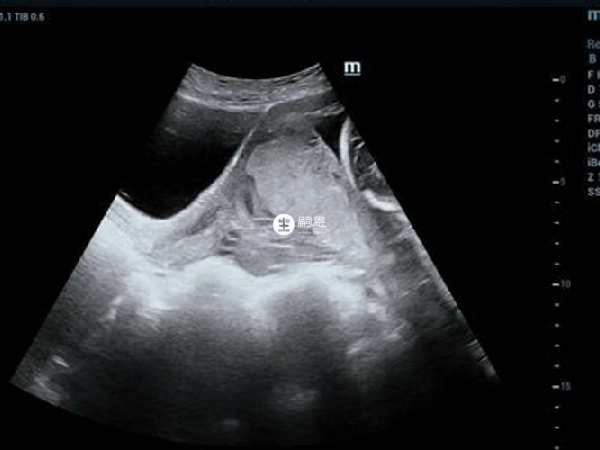

中央性前置胎盘发生难产大出血死亡率非常高,因为在妊娠晚期由于子宫不规则收缩,导致胎盘组织与子宫发生错位,导致胎盘组织完全覆盖宫颈口,胎儿在宫腔内没有充足的氧气,容易窒息,而且孕妇输血不及时,也可能导致死亡:

产妇在确诊胎盘前置后需绝对卧床休息,纠正贫血并使用抗生素预防感染,同时严密观察病情并进行相关辅助检查。